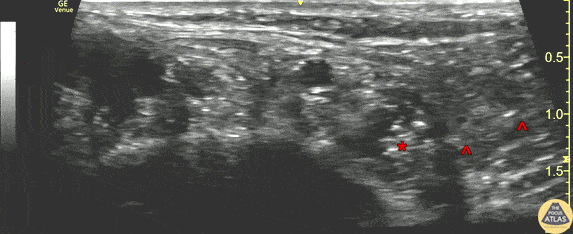

A 20s y/o patient presented after a laceration to the plantar surface of the foot from glass. After exclusion of retained foreign body by XR and physical exam, the laceration was irrigated and repaired using local infiltration of anesthesia, and the patient was discharged. The patient re-presented to the ED within a few hours with continued pain. The laceration repair was intact, and a posterior tibial nerve block was performed for analgesia. This clip shows the nerve block being performed. The linear probe was placed in a transverse plane, just posterior to the medial malleolus, over the “tarsal tunnel.” The left of this image is anterior, and the right is posterior. The needle (^) can be seen entering from the posterior aspect, infiltrating anesthetic around the tibial nerve (*). The pulsating posterior tibial artery is seen anterior to the nerve. The anatomy of the tarsal tunnel can be recalled by the mnemonic “Tom, Dick, And Very Nervous Harry,” which lists the structures in order of anterior to posterior (tibialis posterior tendon, flexor digitorum longus tendon, posterior tibial artery, posterior tibial vein, tibial nerve, flexor hallucis longus tendon), however the tendons and posterior tibial vein are less well seen in this clip. Dr. James Sutton, PGY-3 Denver Health Residency in Emergency Medicine